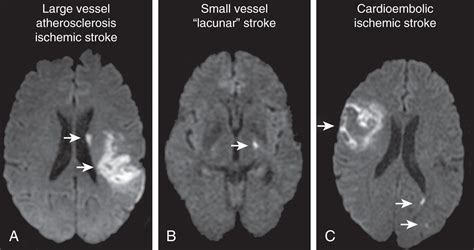

• MRI (Magnetic Resonance Imaging): An MRI can provide even more detailed images of the brain and may be used in cases where the CT scan is unclear or to assess the full extent of the damage. An MRI is better for detecting early changes in the brain tissue.